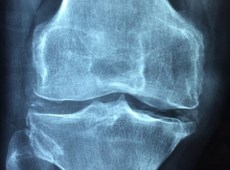

Medicina d’avanguardia in Sicilia, il robot “Omnibotics” per la chirurgia protesica del ginocchio

Già nei mesi scorsi il reparto di chirurgia ortopedica, guidato dal dott. Emanuele Lombardo all’interno dell’istituto ortopedico Villa Salus, ha avviato l’utilizzo, per la prima volta nell’isola, del modernissimo robot di ultima generazione "Omnibotics".